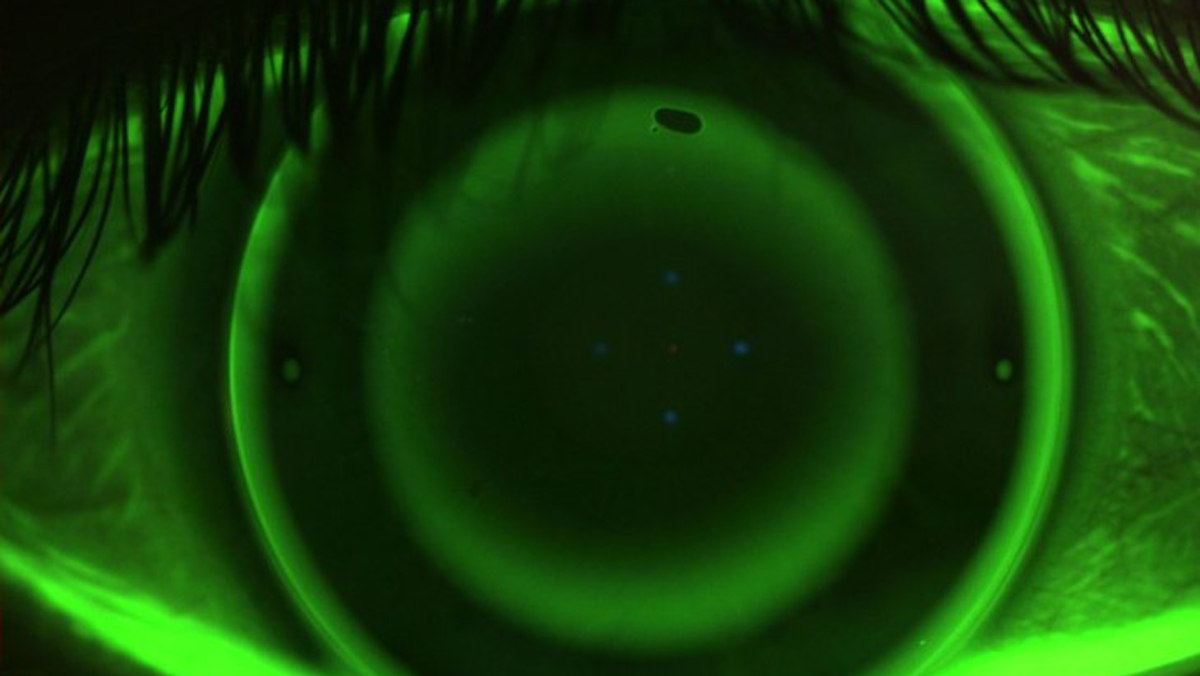

Ungefähr drei Zehntel Radiendifferenz sei eine angemessene Indikation für eine torischen Ortho-K-Linse, so der Experte weiter. Den Angaben zufolge handelt es sich bei der "sleeplens T" um eine "periphertorische Ortho-K Linse, die eine gleichmäßige Auflage der Linse auf der Hornhaut ermöglicht". Die Parameterbestimmung erfolge durch die Angabe der Refraktion, der Hornhautradien, der Exzentrität und dem Hornhautdurchmesser.

Anhand der überlieferten Daten entscheidet Techlens dann für die torische oder sphärische Variante, so Laubenbacher. Bislang seien mit der torischen Ortho-K Linse Hornhautastigmatismen bis circa 2,5 dpt Zylinder auskorrigiert worden.